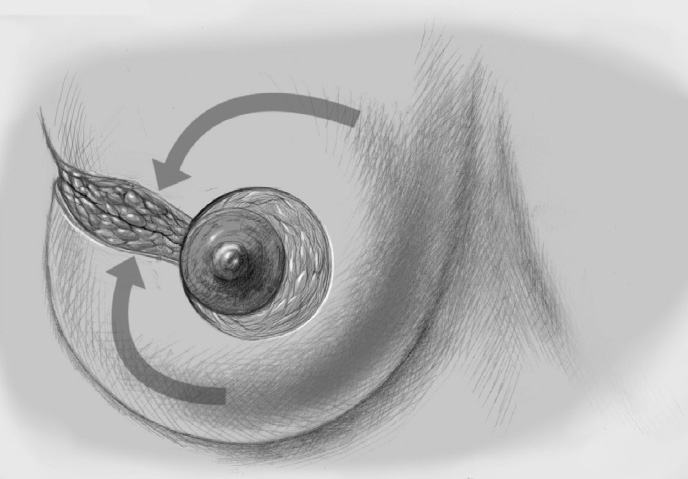

The adjacent parenchyma is mobilized subcutaneously so that the defect can be filled with lobes of breast tissue. Mobilization means exposing the breast relative to the skin or muscle to achieve adequate mobility of < 25% or > 25% as required.

To cover the defect, the glandular lobes are mobilized from the adjacent parenchyma after subcutaneous dissection. The principle of intramammary lobe creation is to mobilize large parts of the breast (> 25%) either relative to the skin or relative to the pectoralis muscle. This “liberation” of the breast from one of its two planes of fixation allows adequate dissection and rotation of sufficient breast tissue. The Y-flap and rotation flap shown in Chapter 3.2.1 are examples of intramammary dissection.